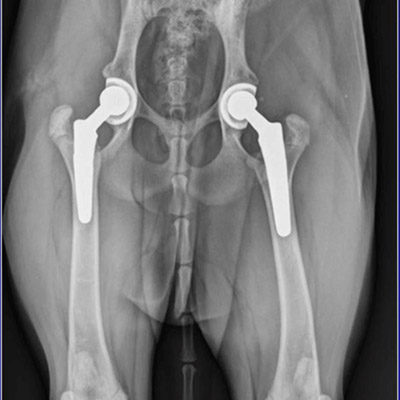

There are two major types ofartificial hip replacements:

A cemented prosthesis is held in place by a type of epoxy cement that attaches the metal to the bone. An uncemented prosthesis bears a fine mesh of holes on the surface that allows bone to grow into the mesh and attach the prosthesis to the bone.

Both are still widely used. In some cases a combination of the two types is used in which the ball portion of the prosthesis is cemented into place, and the socket not cemented. The decision about whether to use a cemented or uncemented artificial hip is usually made by the surgeon based on your age and lifestyle, and the surgeon's experience.

Each prosthesis is made of two main parts. The acetabular component (socket) replaces the acetabulum. The acetabular component is made of a metal shell with a plastic inner liner that provides the bearing surface. The plastic used is so tough and slick that you could ice skate on a sheet of it without much damage to the material.

The femoral component (stem and ball) replaces the femoral head. The femoral component is made of metal. Sometimes, the metal stem is attached to a ceramic ball.